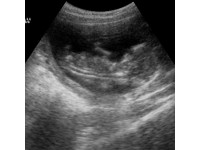

CANINE PREGNANCY AND ULTRASOUND IMAGING

The gestation period greatly varies across species, ranging from the mammoth 480-590 day gestation of the sperm whale, to the more modest 340 equine gestation (I had to mention the horse!), to the relatively minute 21 day gestation of the mouse. The dog has a gestation period of around 61 days, which can be divided into four main stages. It is important for both breeders and veterinarians alike to be familiar with these stages to ensure that the pregnant dog is given the best possible care, and the pregnancy runs smoothly.